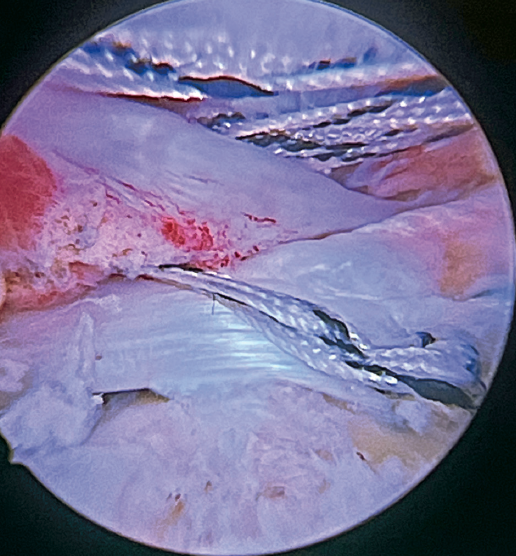

Previously, at intra-articular level, we assessed the quality of the LPB and its insertion in the supraglenoid tuberosity; from subacromial, having prepared the bony footprint on the greater tuberosity, we proceed to release the proximal portion of the tendon from the bicipital groove. The upper part of the transverse humeral ligament is sectioned to mobilize the LPB without damaging it (Figure 2). At this time, the mobility and integrity of the LPB is checked with tendon pulling forceps (Figure 3).